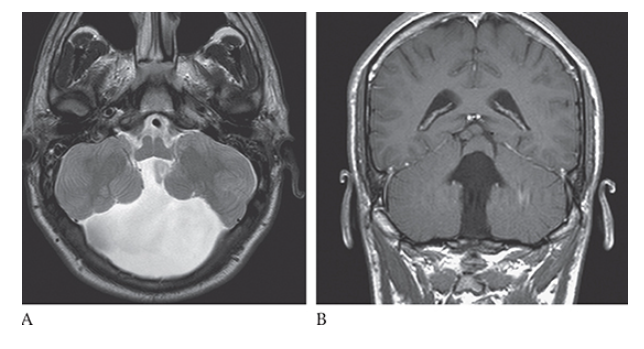

Dandy-Walker Syndrome. Axial NECT shows a large posterior fossa with a CSF density cyst, hypoplastic cerebellar hemispheres, and absence of the vermis.

Dandy-Walker Syndrome. Sagittal T1W image shows a massively dilated fourth ventricle, expanded posterior fossa, high-riding torcula, and hypoplastic cerebellum.

What is A

Dandy-Walker Syndrome. Axial T2W and coronal T1W

What is B

Dandy-Walker Syndrome. Axial T2W show absence of the cerebellar vermis.